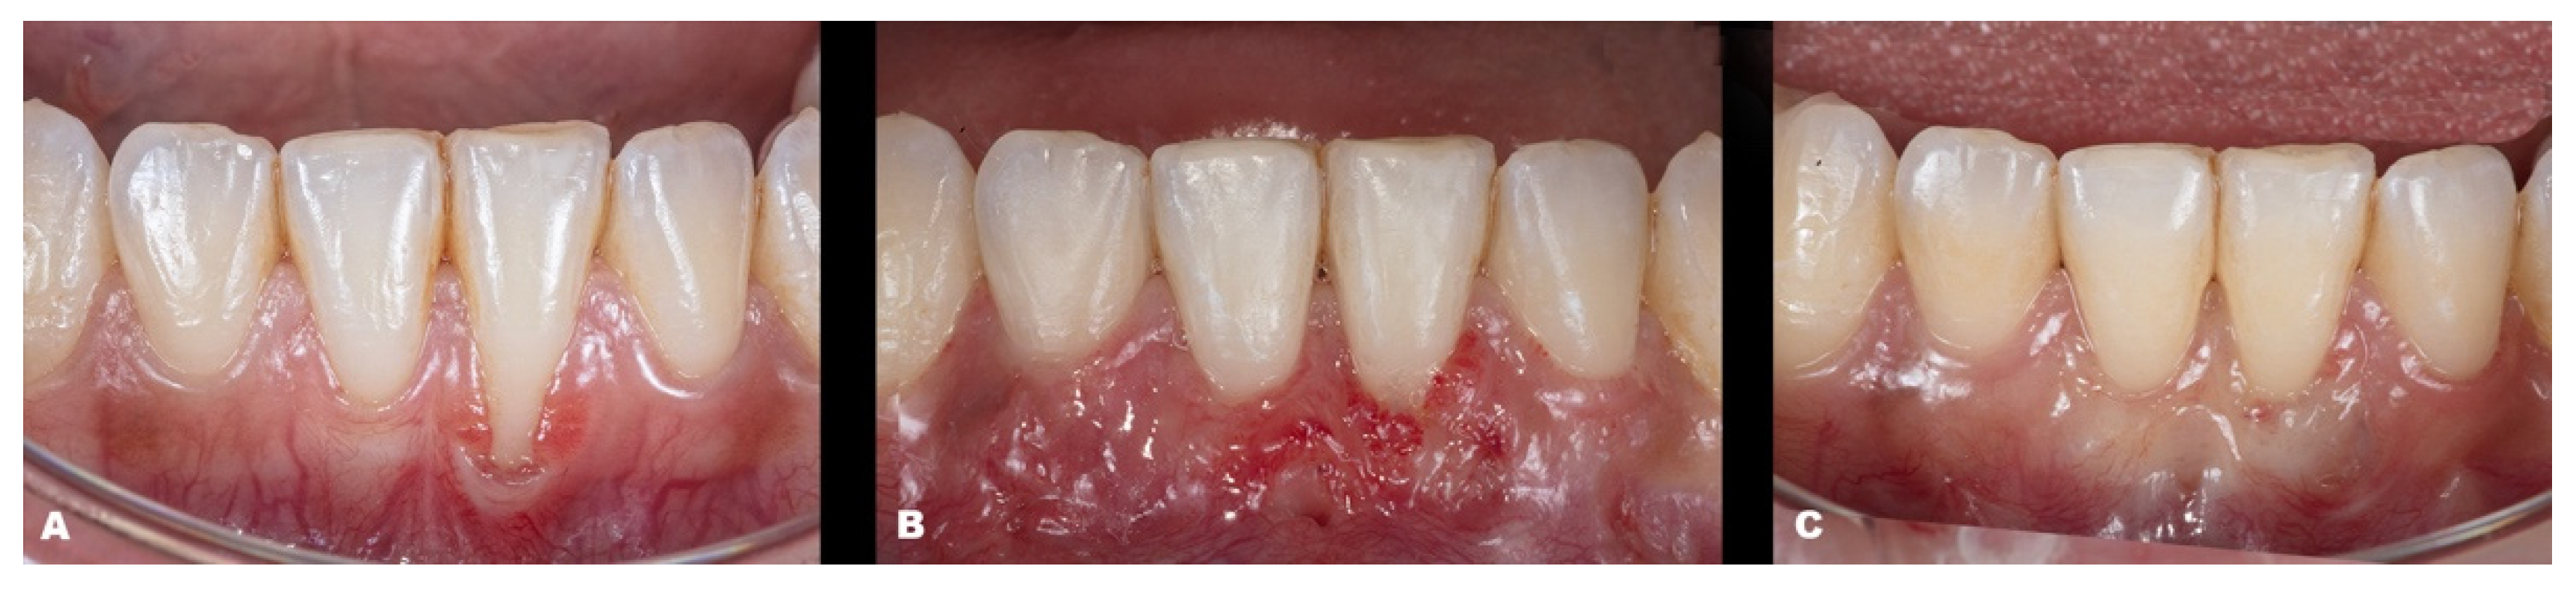

| Classification | Gender | Tooth/Teeth with REC | Initial REC Height (mm) | Initial REC Width (mm) | Initial PD (mm) | Initial KTW (mm) | Final REC Height (mm) | Final PD (mm) | Final KTW (mm) | % RC | p-Value | |

|---|---|---|---|---|---|---|---|---|---|---|---|---|

| Baseline | 6-Month Follow-up | |||||||||||

| Case 6 | RT1 | F | 43 44 45 | 1.2 2.1 1.4 | 2.6 3.1 2.8 | 2.0 1.5 1.0 | 3.0 3.8 3.8 | none | 1.5 1.0 1.0 | 2.1 2.8 5.3 | 100 100 100 | |

| Case 7 | RT1 | F | 12 11 21 22 | 1.1 1.5 2.4 1.5 | 1.5 3.0 4.0 2.0 | 1.0 2.0 1.5 2.0 | 5.4 5.0 6.3 6.9 | none | 1.0 2.5 2.5 1.5 | 4.3 5.7 6.0 6.3 | 100 100 100 100 | |